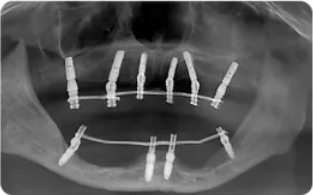

?种植牙前后口内数字化影像 , 左侧为种牙前 , 右侧为种牙后 。

文章图片

针对这种情况 , 吴博士根据患者口内各项情况 , 最终制定“即刻种”和“生长因子种植牙技术”方案 。 按照术前制定的位点和角度 , 在上半口植入6颗植体 , 从而增加稳定性;下半口植入4颗植体 , 最终以10颗植体当天完成全口种植修复 , 并当天完成过渡性义齿修复 。